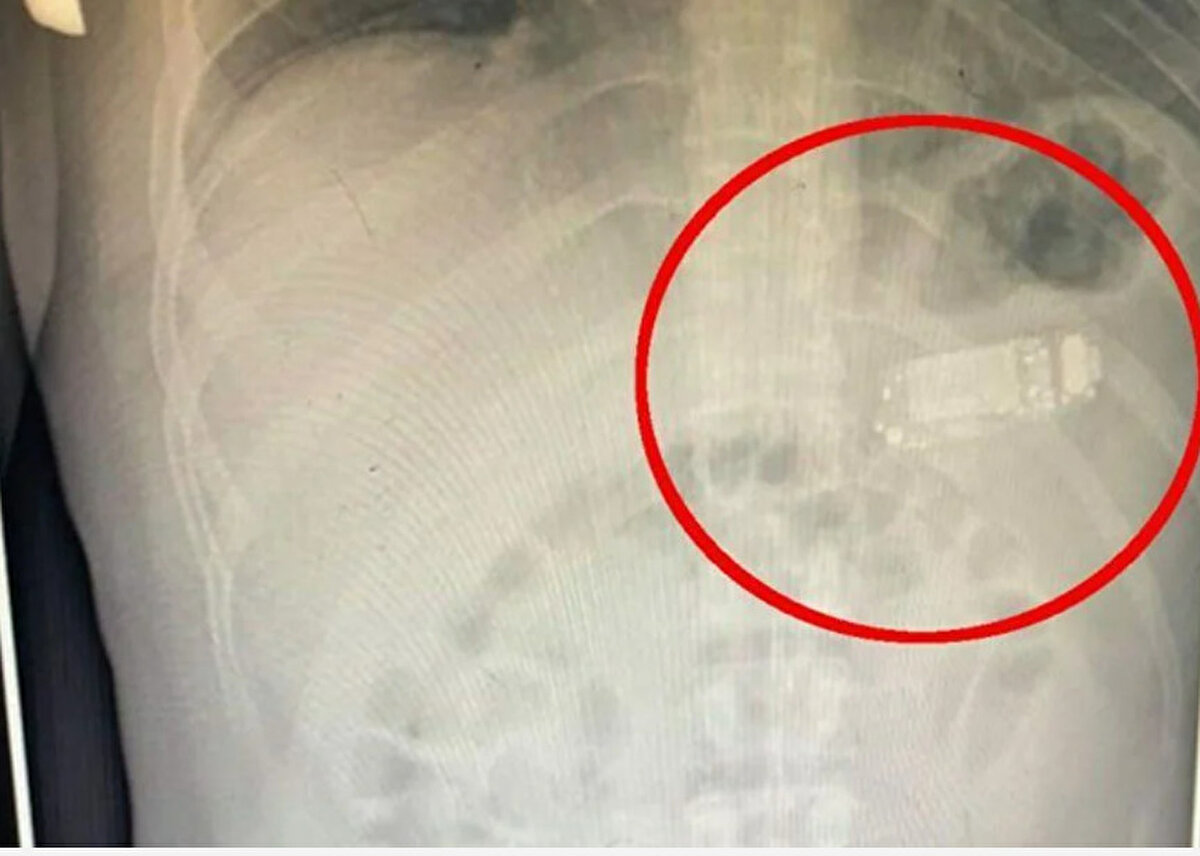

Güneydoğu Avrupa'da denize kıyısı olmayan bir ülke olan Kosova'nın başkenti Priştine'de doktorlar, Nokia 3310 model bir cep telefonunu yutan adamı ameliyat etti. Telefonun adı açıklamayan adamın midesinde dört gün kaldığı belirtildi. Başarılı operasyonu gerçekleştiren sağlık ekibinin başındaki doktor Skender Teljaku, adamın midesinden çıkarılan telefonun fotoğrafları ile röntgen ve endoskop görüntülerini Facebook'ta yayınladı.

Teljaku yaptığı açıklamada, tıbbi ekibin telefonu mideyi kesmeden, endoskop olarak bilinen özel cihazlar kullanarak üç ayrı parçaya ayırmayı başardığını söyledi. Teljaku, ayrıca yaklaşık iki saat süren işlem sırasında "herhangi bir komplikasyon" yaşanmadığını sözlerine ekledi. Bununla birlikte 33 yaşındaki adamın telefonu yuttuktan sonra yaşadığı acı nedeniyle Kosova'nın başkentindeki hastaneye gitmeye karar verdiği aktarıldı. Teljaku, özellikle bataryanın en tehlikeli parçası olduğunu, patlayarak hayatı potansiyel olarak tehlikede olan adamın bağırsaklarına kimyasal salabileceğini söyledi.